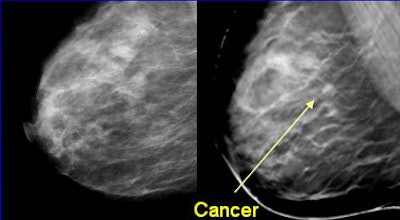

| Left, conventional full-field digital mammogram (FFDM). Right, DBT exam. All images courtesy of Dr. Daniel Kopans, senior radiologist at Massachusetts General Hospital, and Richard Moore, director of Kopans' breast imaging research projects. |